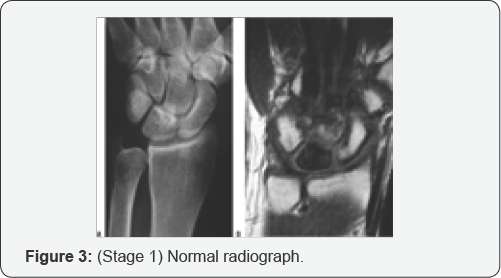

In early stages of this disease, the x-rays may be normal and other tests are needed to confirm the diagnosis. Most likely, the most reliable test to assess the blood supply of the lunate is Magnetic Resonance Imaging (MRI), CT scanning, specialized CT scanning and bone scan may also be used (Figure 2). The Stahl classification of Kienböck's disease, modified by Lichtman, is the most commonly used staging system and is useful in the treatment of Kienböck's disease (avascular necrosis of the lunate) [7]. This system divides the disease into four stages (Figures 3-6):

i. Stage I: normal radiograph.